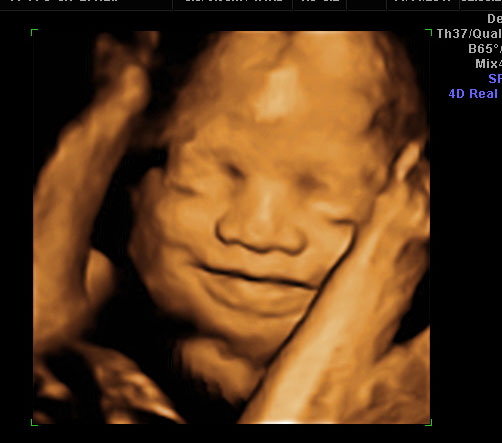

Hawaii Essure Reversal Baby On The Way!

It’s a boy! My family and I couldn’t feel more blessed.

The Essure reversal surgery was definitely worth every penny. I’m so excited to be welcoming a boy after being a mother of 3 girls. It’s a dream come true. I’m due to have my C-section this upcoming January 2018.